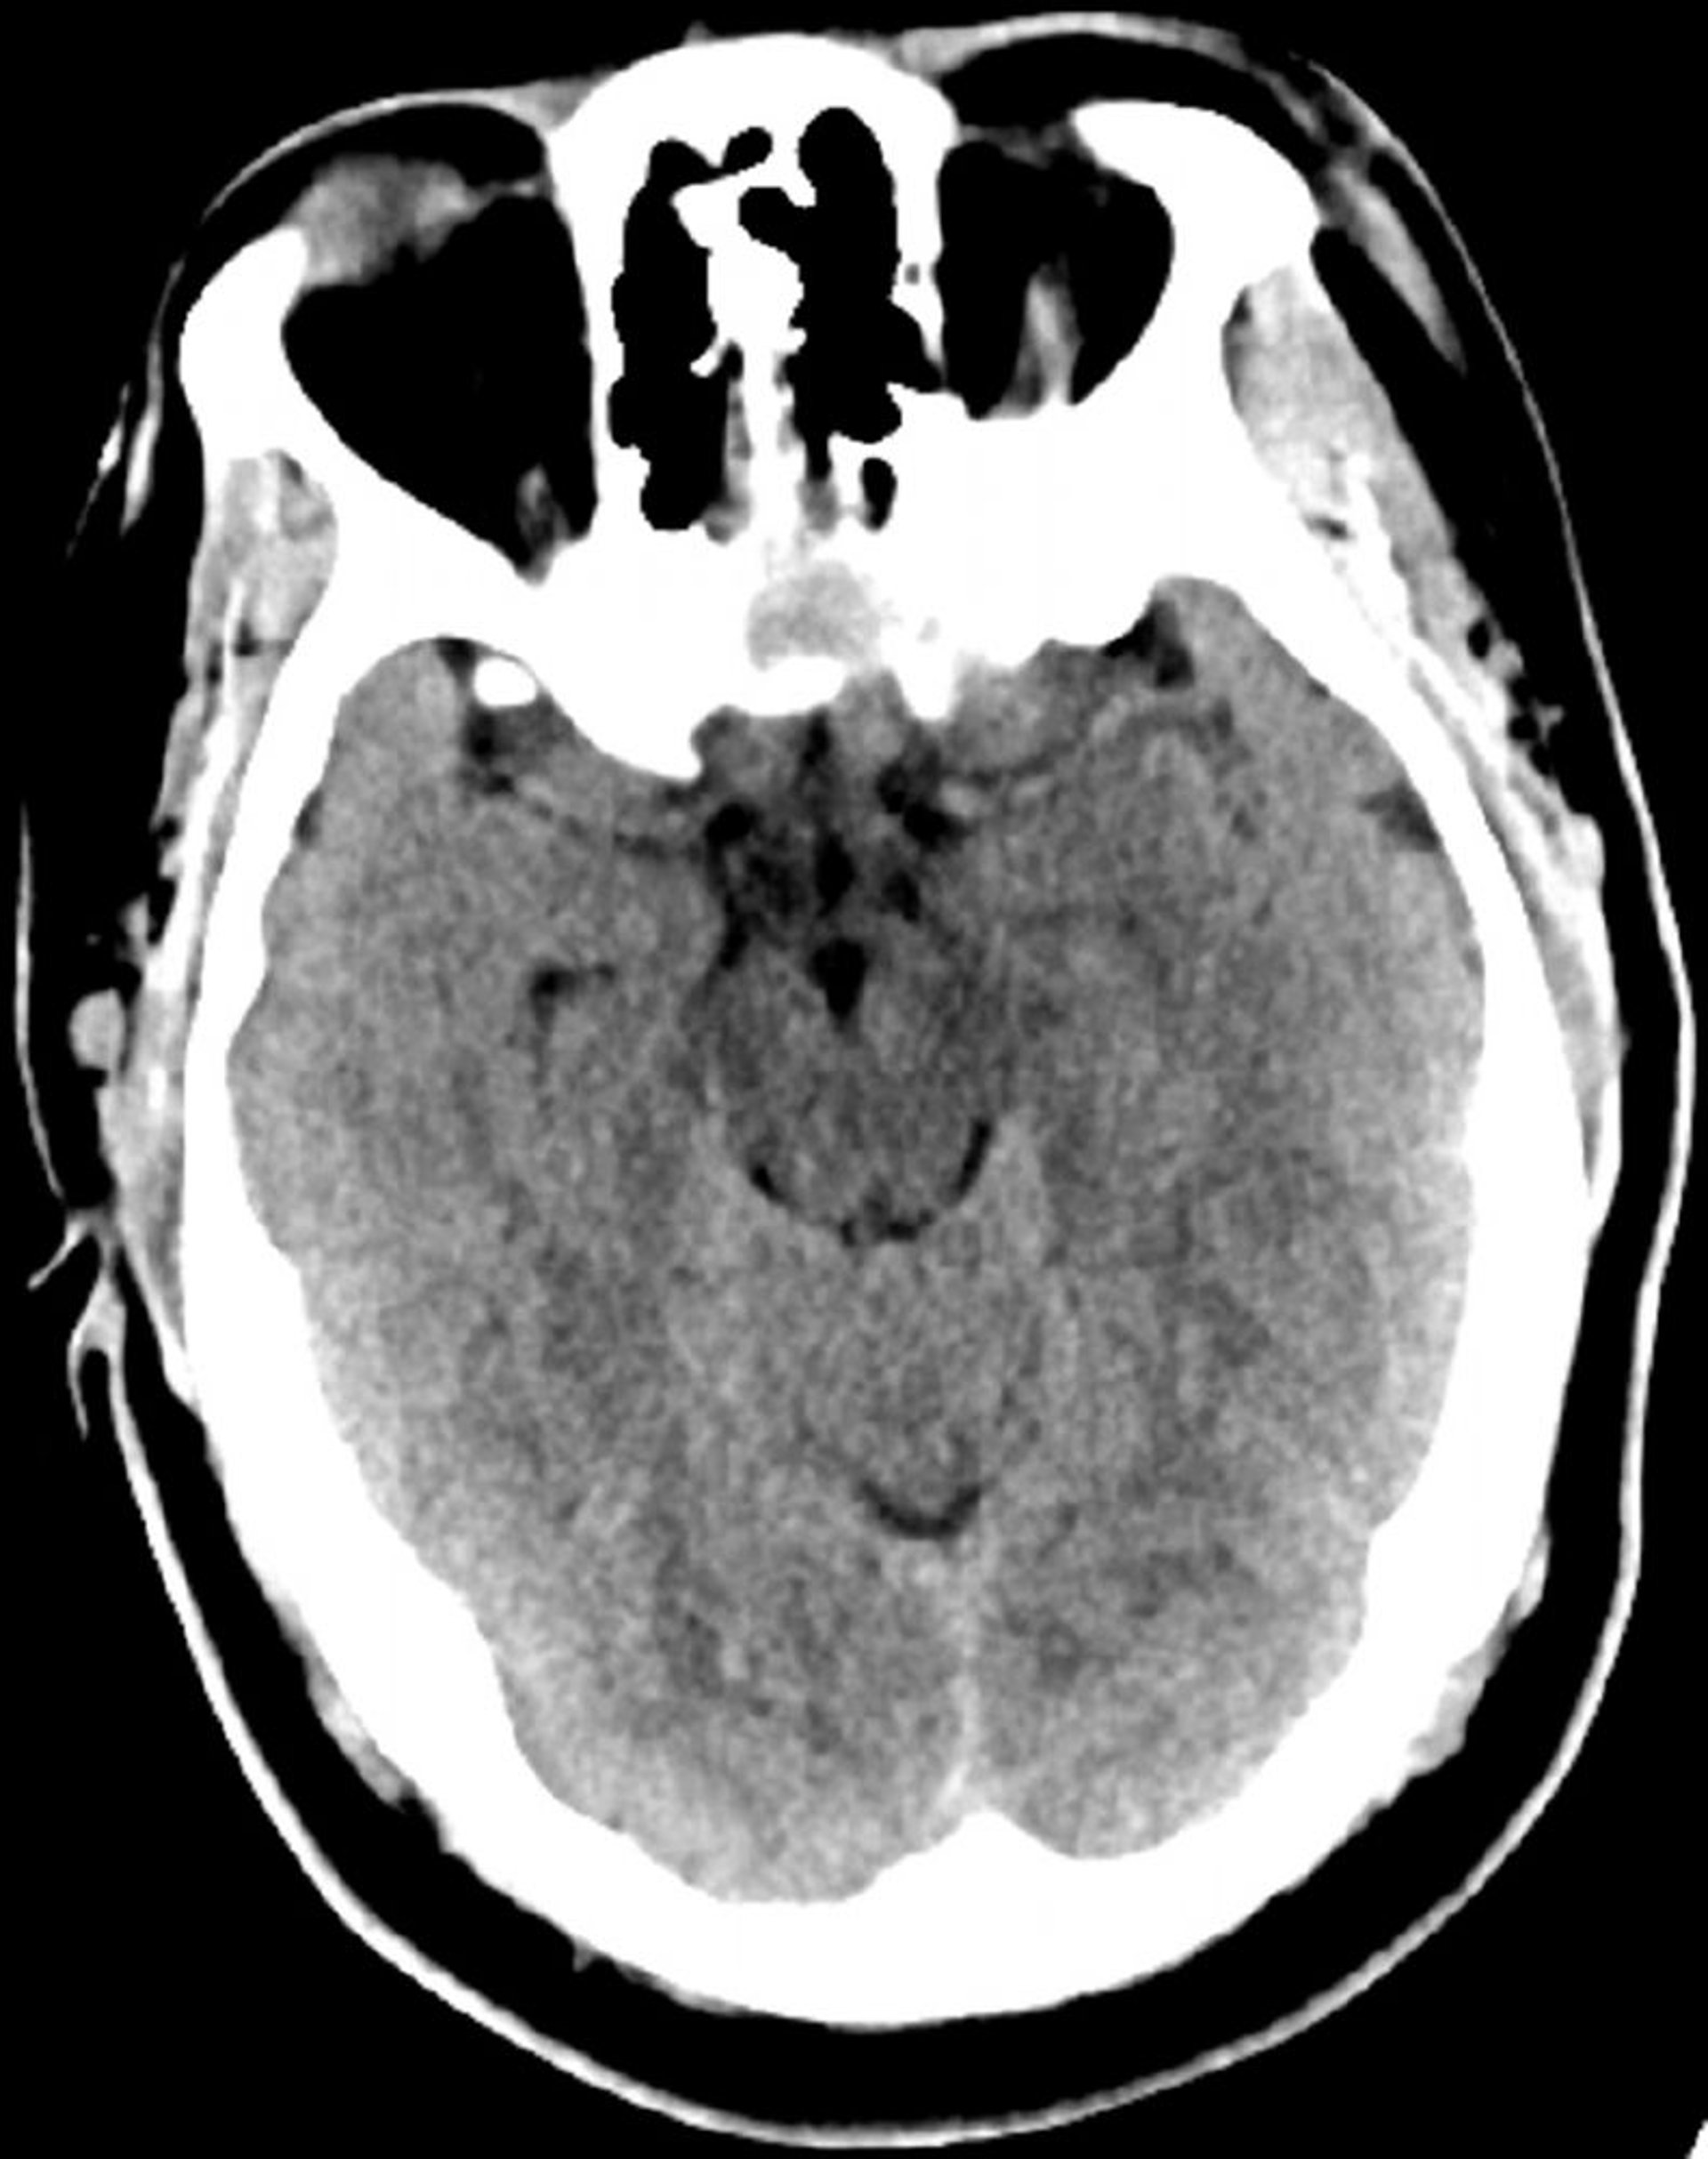

TC cerebrale normale (adulto di 30 anni), slide 6

Questa immagine è una normale TC della testa di un adulto di 30 anni. Non vi è alcun liquido o emorragia intra o extra assiale. La differenziazione grigio-bianca è preservata. Le dimensioni ventricolari e il disegno dei solchi sono normali.